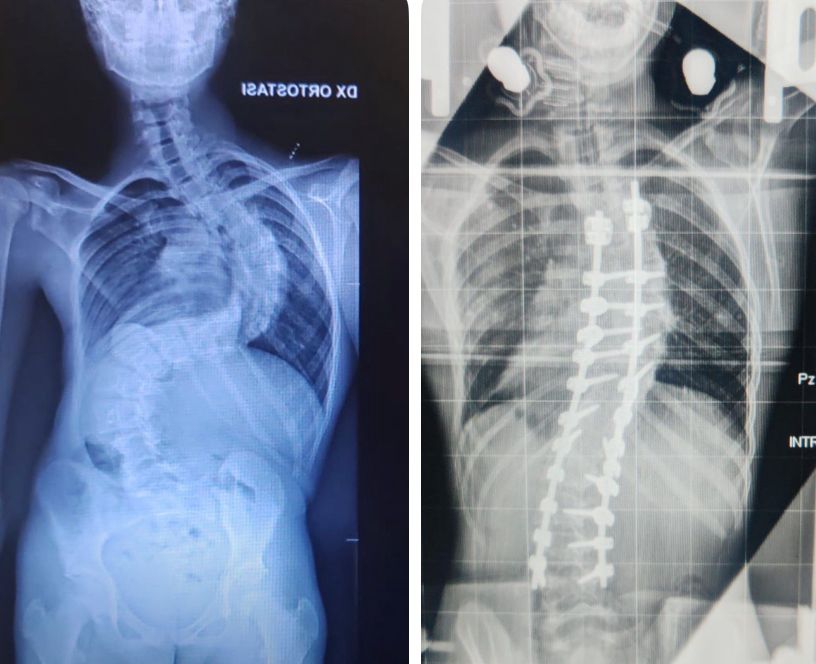

BARI - Dopo oltre un mese trascorso in ospedale, Francesco potrà finalmente tornare a casa e vivere il Natale accanto alla sua famiglia. Il ragazzo, 13 anni, era ricoverato presso il Policlinico di Bari per affrontare un delicato e articolato trattamento ortopedico necessario a correggere una scoliosi severissima di 117 gradi, una condizione che negli ultimi mesi aveva mostrato una progressione particolarmente aggressiva.

Secondo quanto spiegato dal dottor Piazzolla, la situazione clinica presentava elementi di estrema complessità. In soli 3 mesi, la curvatura della colonna era peggiorata di oltre 30 gradi, rendendo indispensabile una preparazione preoperatoria lunga e accurata. Per più di 1 mese, Francesco ha vissuto stabilmente in reparto, sottoposto a una trazione continua mediante un dispositivo speciale, l’halo, che ha permesso di preparare gradualmente la colonna vertebrale all’intervento chirurgico. Grazie a questo percorso, la scoliosi è stata ridotta a 45 gradi prima dell’operazione definitiva.

La radiografia prima e dopo l'intervento al Policlinico di Bari